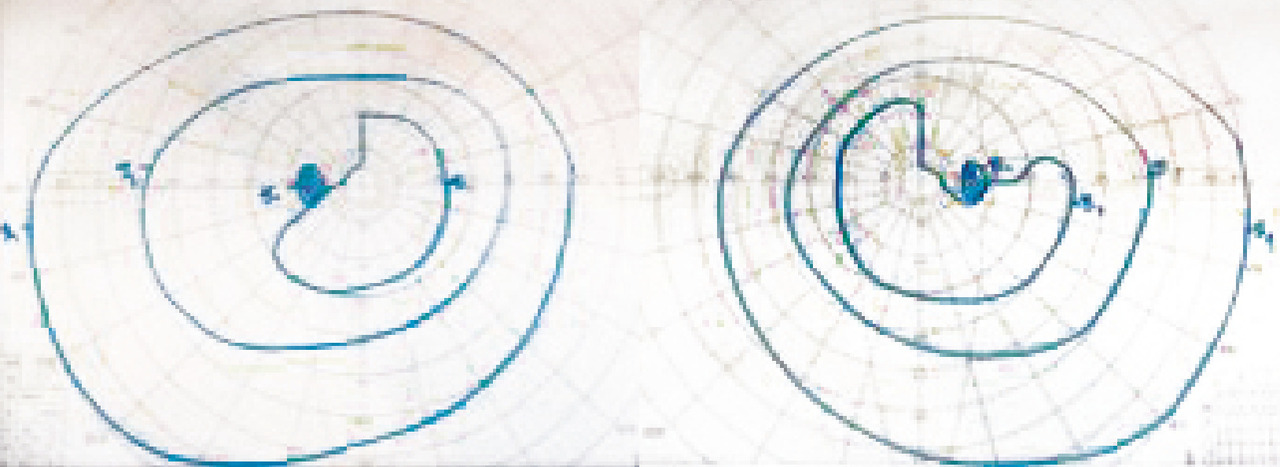

Anomalies du champ visuel

Les atteintes du champ visuel sont souvent difficiles à caractériser sans examen complémentaire, d’autant plus lorsqu’elles sont bilatérales. L’interrogatoire et la réalisation d’un champ visuel au doigt en cachant un œil ou sur une feuille de papier en dessinant ce qui manque permet de s’orienter lorsque la réalisation d’un champ visuel standard n’est pas possible en urgence (fig. 1).

Atteinte bilatérale : principalement chiasma et en arrière du chiasma

Dans l’atteinte chiasmatique ou rétrochiasmatique, on observe une atteinte bilatérale avec respect du méridien vertical. Au niveau du chiasma, l’hémianopsie est bitemporale, alors qu’en arrière du chiasma une lésion unilatérale donne une hémi- ou quadranopsie latérale homonyme controlatérale à la lésion.

Atteinte du chiasma optique

Le syndrome chiasmatique donne classiquement une quadranopsie bitemporale supérieure évoluant vers une hémianopsie bitemporale. Les causes sont dominées par les tumeurs hypophysaires, dont l’adénome hypophysaire et plus rarement le craniopharyngiome ou un méningiome (fig. 3).

Atteintes des radiations optiques

Elles entraînent une quadranopsie (voire hémianopsie) latérale homonyme et opposée à la lésion. Par exemple, une atteinte de la radiation inférieure (temporale) droite est responsable d’une quadranopsie supérieure gauche et une atteinte supérieure (pariétale) d’une quadranopsie inférieure controlatérale. Les causes sont les mêmes que dans le cadre des atteintes des bandelettes optiques (fig. 4).

Atteinte du cortex visuel

Les atteintes occipitales sont responsables d’hémianopsie latérale homonyme « à couper au couteau » controlatérale à la lésion (fig. 5). Dans le cas d’une atteinte bilatérale (AVC du tronc basilaire), l’atteinte peut aller jusqu’à la cécité corticale. Les patients ont classiquement une conservation du réflexe photomoteur et une anosognosie, rendant le diagnostic difficile. Les causes sont les mêmes que celles des atteintes des bandelettes et des radiations optiques avec, en cas d’atteinte bilatérale, des causes toxiques, comme l’intoxication au monoxyde de carbone (CO).